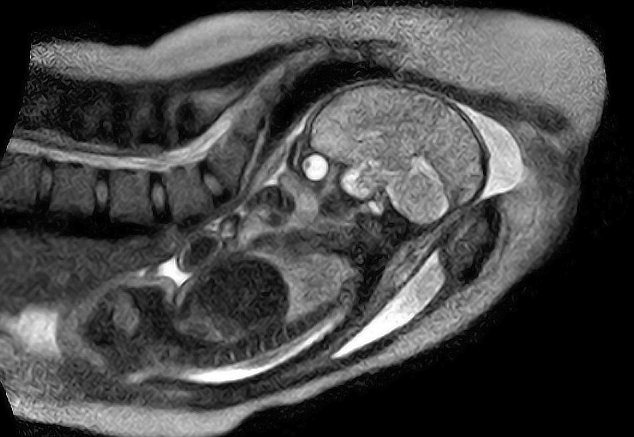

世界初! 出産時の胎児の様子をMRIで撮影。

ベルリンの病院で、世界で初めて出産の様子がMRI撮影されました。上の画像がそれです。 今まさに母親の中の世界から外に出ようとしている赤ちゃんがとても鮮明に美しく写っていますね。ベルリンの Charite病院で、特別な「オープンタイプ」のMRIスキャナー(通常はチューブのような形状をしている)を用いり、出産のためのスペースを充分に確保、出産の時の赤ちゃんの様子をMRIで撮影したそうです。

これは出産における胎児の細かい動きなど、あくまでも科学的な事由においてのみ使うと約束された上での撮影でした。このリアルなMRI画像は、合併症や出産時のプロセスの落とし穴を理解する上で、重要な証拠となるのだそうです。

興味深いわコレ。

赤ちゃんが硬い脊椎に対し、産道を切り開いていくのが判る。

道理で出産の時は背中が痛い訳だ。